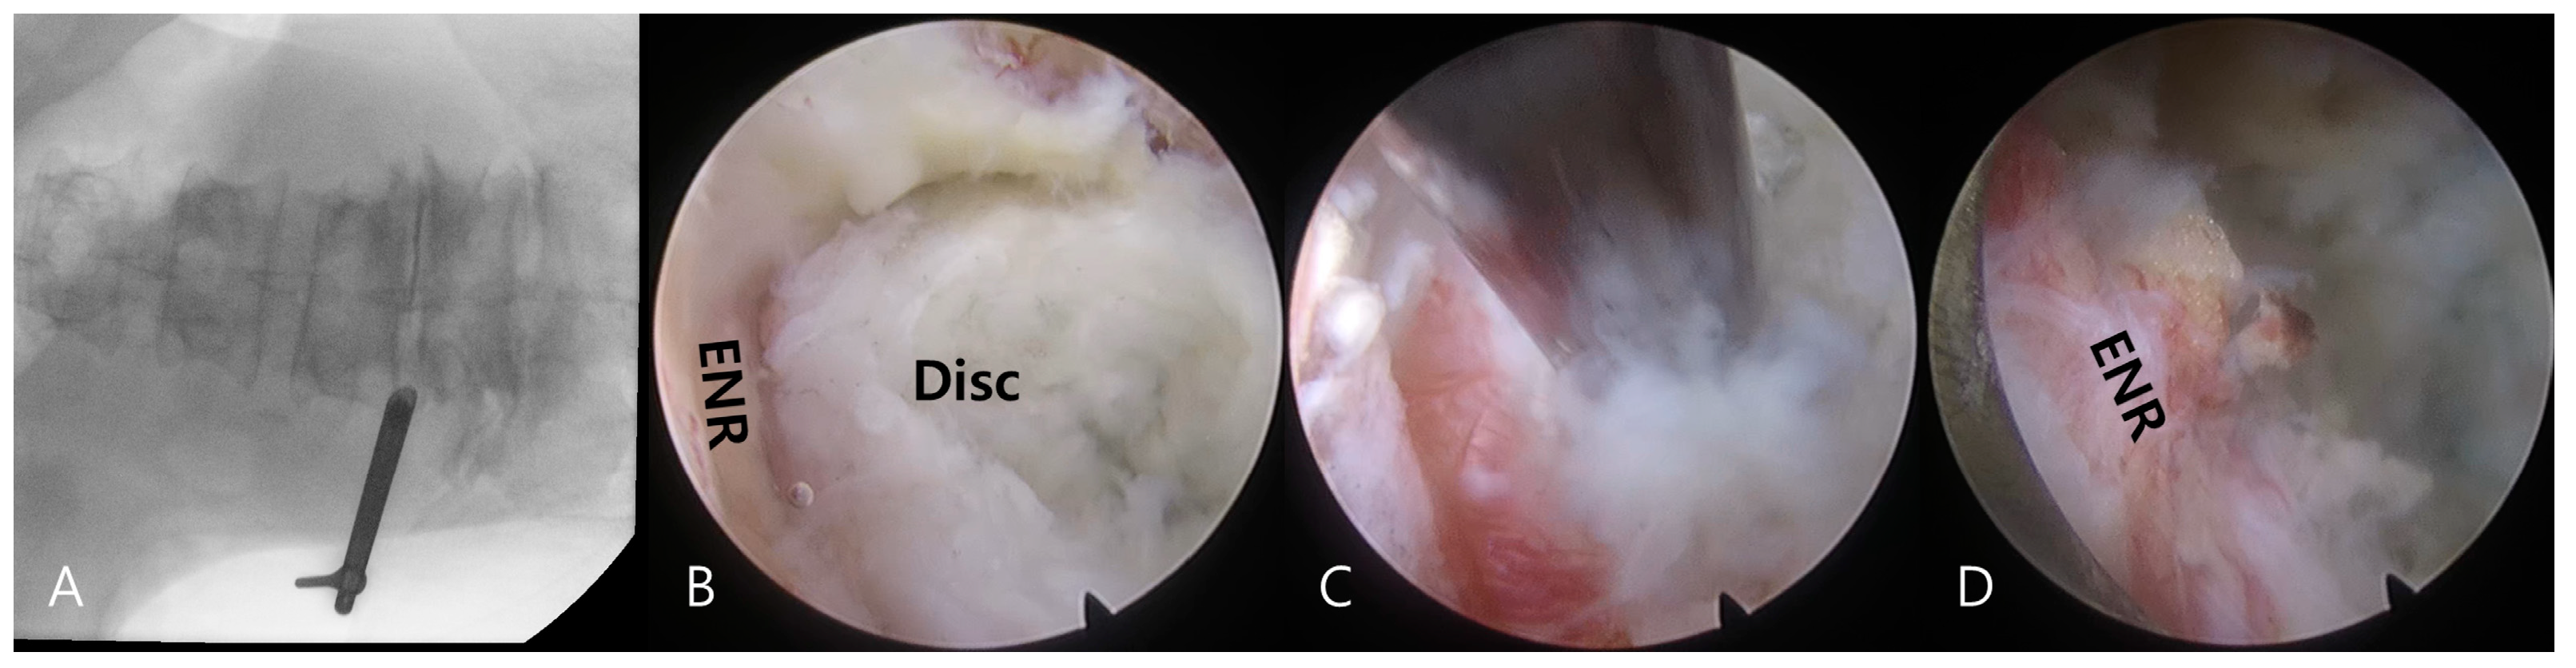

Transforaminal endoscopic lumbar discectomy was performed using the transforaminal approach under local anesthesia combined with sedation as needed [16,17]. Premedication included intramuscular administration of midazolam (0.05 mg/kg) and intravenous administration of fentanyl (0.8 μg/kg) on call. Additional fentanyl doses were administered as required depending on the patient’s vital signs and sedation level. The patients were then placed in a prone position, with their knees flexed on a radiolucent spine table. The procedure comprised two processes, namely (1) a transforaminal percutaneous approach under fluoroscopic guidance and (2) selective discectomy under direct endoscopic visualization (Figure 3).

Figure 3.

Intraoperative images during transforaminal endoscopic lumbar discectomy for a left extraforaminal lumbar disc herniation at the L4–5 level. Fluoroscopic images demonstrate the docking of the working sheath and the exploration of the foraminal and extraforaminal zones (A). Transforaminal selective discectomy is performed under endoscopic visualization. Note the herniated disc fragment (Disc) compressing the exiting nerve root (ENR) (B). The herniated disc fragment is removed using an endoscopic forceps (C). The final endoscopic view shows decompression of the ENR (D). The successful completion of the procedure is confirmed by free mobilization and a strong pulsation of the nerve root.

Under fluoroscopic guidance, an 18-G needle was percutaneously inserted posterolaterally at approximately a 45° angle. The needle was inserted into the disc through the foraminal window, and intraoperative discography was performed using a contrast medium and indigo carmine. A sequential dilation technique was then employed until the working sheath was docked at the foraminal zone, outside or inside the disc surface (Figure 3A).

An ellipsoidal working channel endoscope was introduced through the working sheath, initiating a thorough selective discectomy under endoscopic visualization. Herniated disc fragments and compressed neural tissues were visualized (Figure 3B) and distinguished using instrumental dissection with a probe, forceps, and a radiofrequency tip. After adequate dissection and release of the annular anchorage, the herniated disc fragments were selectively removed using endoscopic forceps (Figure 3C).

The final point of the procedure was determined by the free mobilization of the nerve root and strong pulsation of the dural sac after sufficient discectomy (Figure 3D).